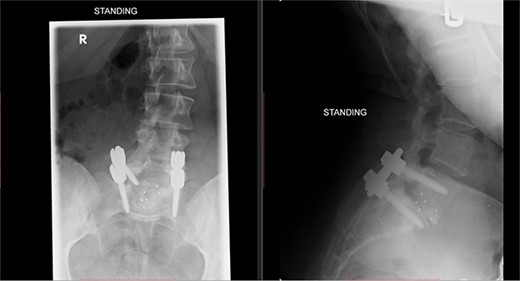

A repeat MRI scan (Fig. 2) performed in December 2016 did not show any interval changes as compared to the scan performed in February 2016. The patient presented elsewhere and was recommended for spinal fusion surgery. A posterior pedicle screw instrumentation with rods and a posterior interbody cage procedure was performed elsewhere in January 2017.

Preoperative MRI of the lumbar spine performed in December 2016. The MRI shows no neurological compression.